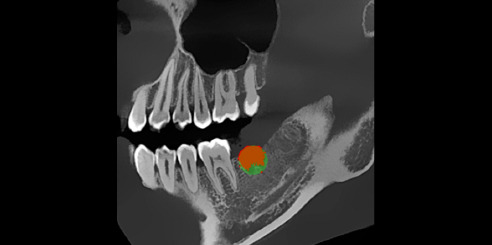

Next, Nerve Detection with Dental CBCT (AI+Nerve)

The system automatically identifies and labels the neural tube within the CT image.

This function simplifies diagnosis and supports more precise surgical planning.

T-MAR Metal Artifact Reduction in LargeV Dental CBCT

With the new T-MAR module, the system automatically removes metal artifacts and corrects image distortions intelligently.

Hence, the final images remain clear, accurate, and clinically reliable.